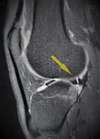

Les lésions méniscales sont des motifs fréquents de consultation en chirurgie orthopédique. L’examen clinique est primordial pour en faire le diagnostic mais il est indispensable de confirmer ces lésions par une IRM, voir un Arthroscanner.

L’IRM (ou l’arthroscanner) confirme l’existence d’une lésion méniscale et sa localisation.